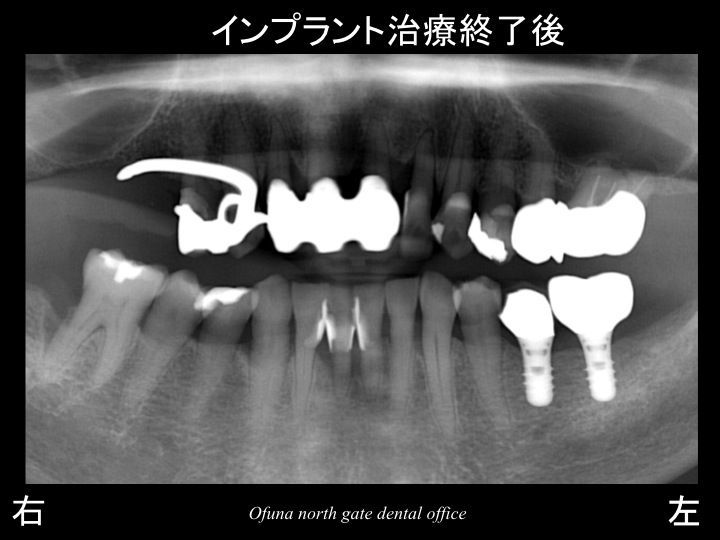

以下が治療終了後です。

下顎左側の奥歯の欠損部にインプラント治療を行うことにより

他の歯への噛む力の負担が少なくなります。

もし、下顎左側にインプラント治療を行わなかった場合には、

残っている歯を支えている骨が少なくなっているため、

どうしても残っている歯の将来性は低くなってしまいます。

最小限で最大の効果を得ることができた症例と言えます。